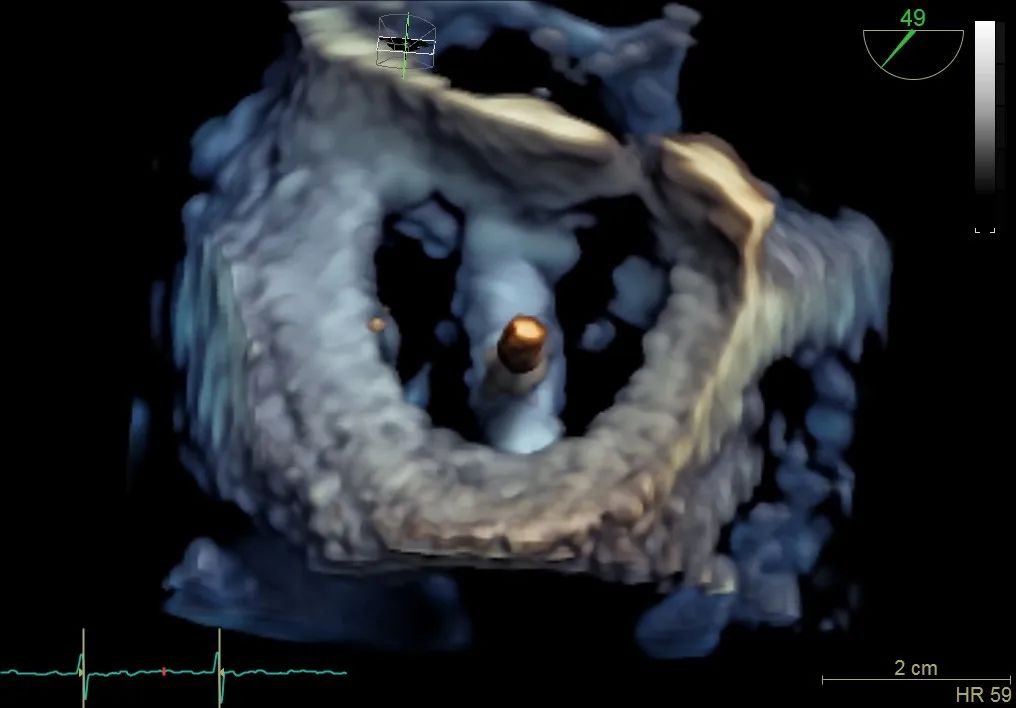

术前食道超声可见二尖瓣重度反流,前后叶对合不全伴有间隙,且反流束宽度18mm

调整二尖瓣夹,使其定位于反流6-12点钟方位

二尖瓣在收缩期变成双孔状,反流有效减小